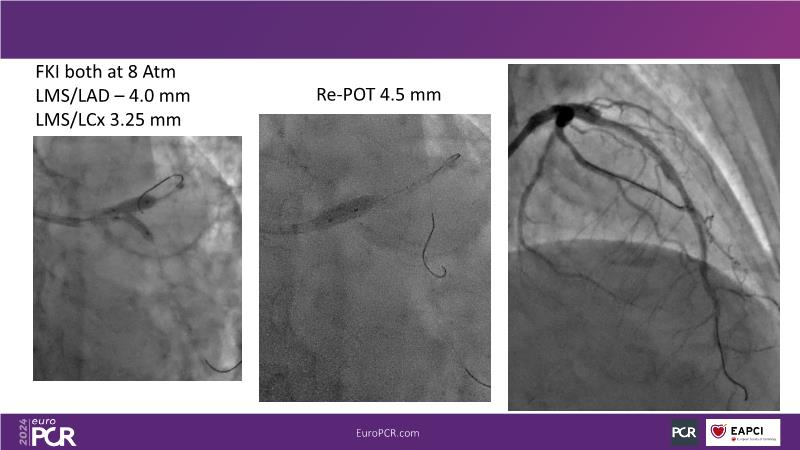

From innovation to reality: the impact of Cre8 EVO technology on complex PCI

This session is a good opportunity to delve into the contemporary technical and clinical complexities surrounding complex PCIs in challenging patient cases. Explore the necessary tools and treatment strategies to enhance peri-procedural and long-term clinical outcomes, and follow discussions on the unique technologies of Cre8 EVO in complex PCI scenarios.

- To find out - through educational clinical cases - how to leverage on accurate evaluation of patient profile, imaging/functional modalities, strategic interventional approach and proper device selection contribute to maximise patient clinical outcome